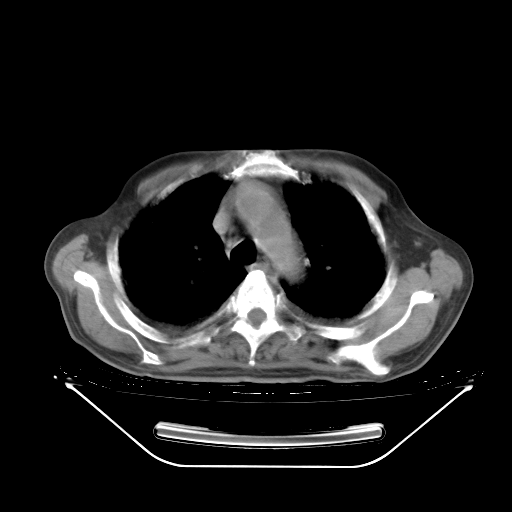

今天复查肺部CT,发现双肺广泛磨玻璃样改变。所以我把3月19日和5月9日相隔50天的肺部CT上传。请大家会诊。

2009年3月19日肺部CT片。

2009年3月19日肺部CT

5月9日肺部CT(在4月27日齐鲁医院肺部CT描述部分肺组织磨玻璃样改变,12天后肺组织广泛磨玻璃样改变)

大致读了系列胸部CT:纵隔窗无明显异常,肺窗:从4、27至今:主要是双肺中下野外带可见毛玻璃样改变,目前处于急性肺泡炎阶段,至于原因考虑1、结替组织或胶原血管性疾病所致?2、恶性疾病如恶组在肺部所致的表现或细支气管肺泡癌?3、药物或其它原因如肺蛋白沉着症所致肺泡炎目前不太可能?总之,明天就去请我院的呼吸科、感染科、血液科和临免专家会诊哈。